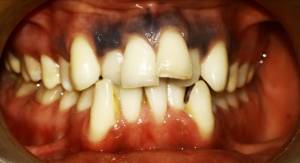

Before Treatment (Initial Assessment)

An initial assessment was carried out to understand the patient’s dental alignment and presenting complaints.

Intraoral Images: — (Before-treatment images)

The patient was diagnosed with Angle’s Class I malocclusion, along with crowded teeth and a crossbite. These conditions caused improper alignment of the teeth and an uneven bite.